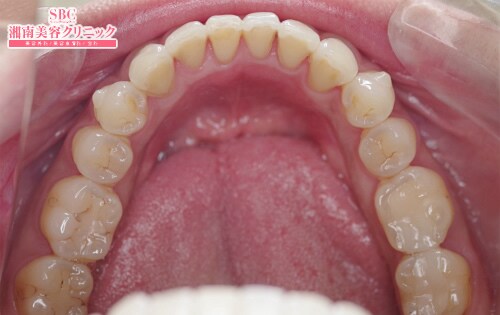

豊田ゆきほ(歯科) 医師

施術前

施術後6ヶ月後

インビザラインgoををされたお客様です。【モニター価格263,500円】『Smile Queen 豊田ゆきほです!歯並びで悩んでいる全ての人を幸せに!歯並びで人生は変わります。女優・モデル・俳優前歯はDr.ゆきほにお任せ下さい。』

インビザラインgoををされたお客様です。

【モニター価格263,500円】

『Smile Queen 豊田ゆきほです!

歯並びで悩んでいる全ての人を幸せに!

歯並びで人生は変わります。

女優・モデル・俳優前歯はDr.ゆきほにお任せ下さい。』